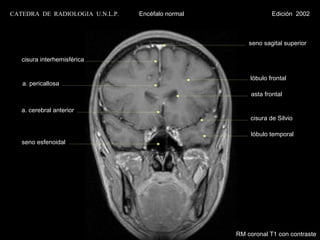

CATEDRA DE RADIOLOGIA U.N.L.P.   Encéfalo normal                Edición 2002

seno sagital superior

cisura interhemisférica

lóbulo frontal

a. pericallosa

asta frontal

a. cerebral anterior

cisura de Silvio

lóbulo temporal

seno esfenoidal

RM coronal T1 con contraste